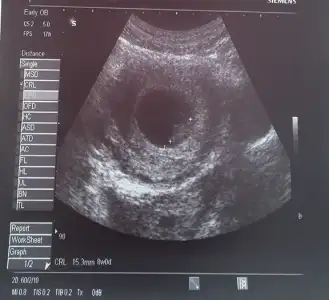

Bu da benim ponçiğim :)

:KK200:Kizlar bebegime bakin çok tatlımasllah ellerimiz ayaklarimz ooluşmuş:KK36::KK9:

ya bu minyatur bi bebek cidden. Masalla:) 9. Haftadaymissin da tam kac hafta kac gunluk? Boyu ne kadar? Cok heyecanli:)